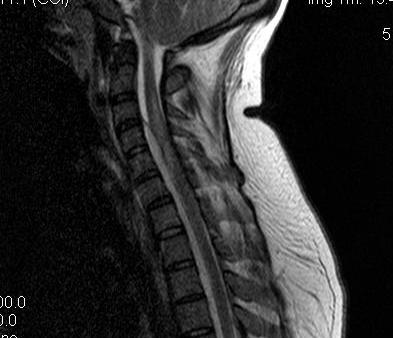

MRI

Investigation of choice

- T1: Low signal intensity mass

- T2: High signal intensity mass

- 85% sensitivity

Gadolinium enhancement T1

- peripherally or homogenous / typical of all abscess on MRI

- increases sensitivity to 95%

Assess levels

- multi level epidural pus

- need multilevel laminectomy and passage of catheter to aid washout

Also assess

- vertebral body osteomyelitis

- cord pathology

- other DDx (HNP, tumour, cord infarct)